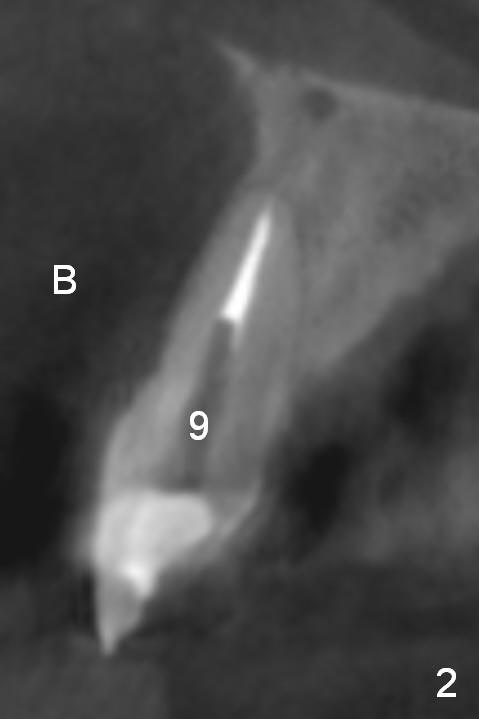

The implant at the site of #8, which was placed ~ 2 years ago, appears devoid of bone buccally (Fig.1 (CBCT 3 D image) I). Fig.2,3 are coronal sections of the tooth #9 (B: buccal) and 8 (A: Zirconium abutment), respectively. Fig.4 is a coronal section of the tooth #5 post-immediate implant with the bone plate (>, different case). With placement of a 15° Titanium abutment (Fig.5 palatal green line), the crown profile may improve.